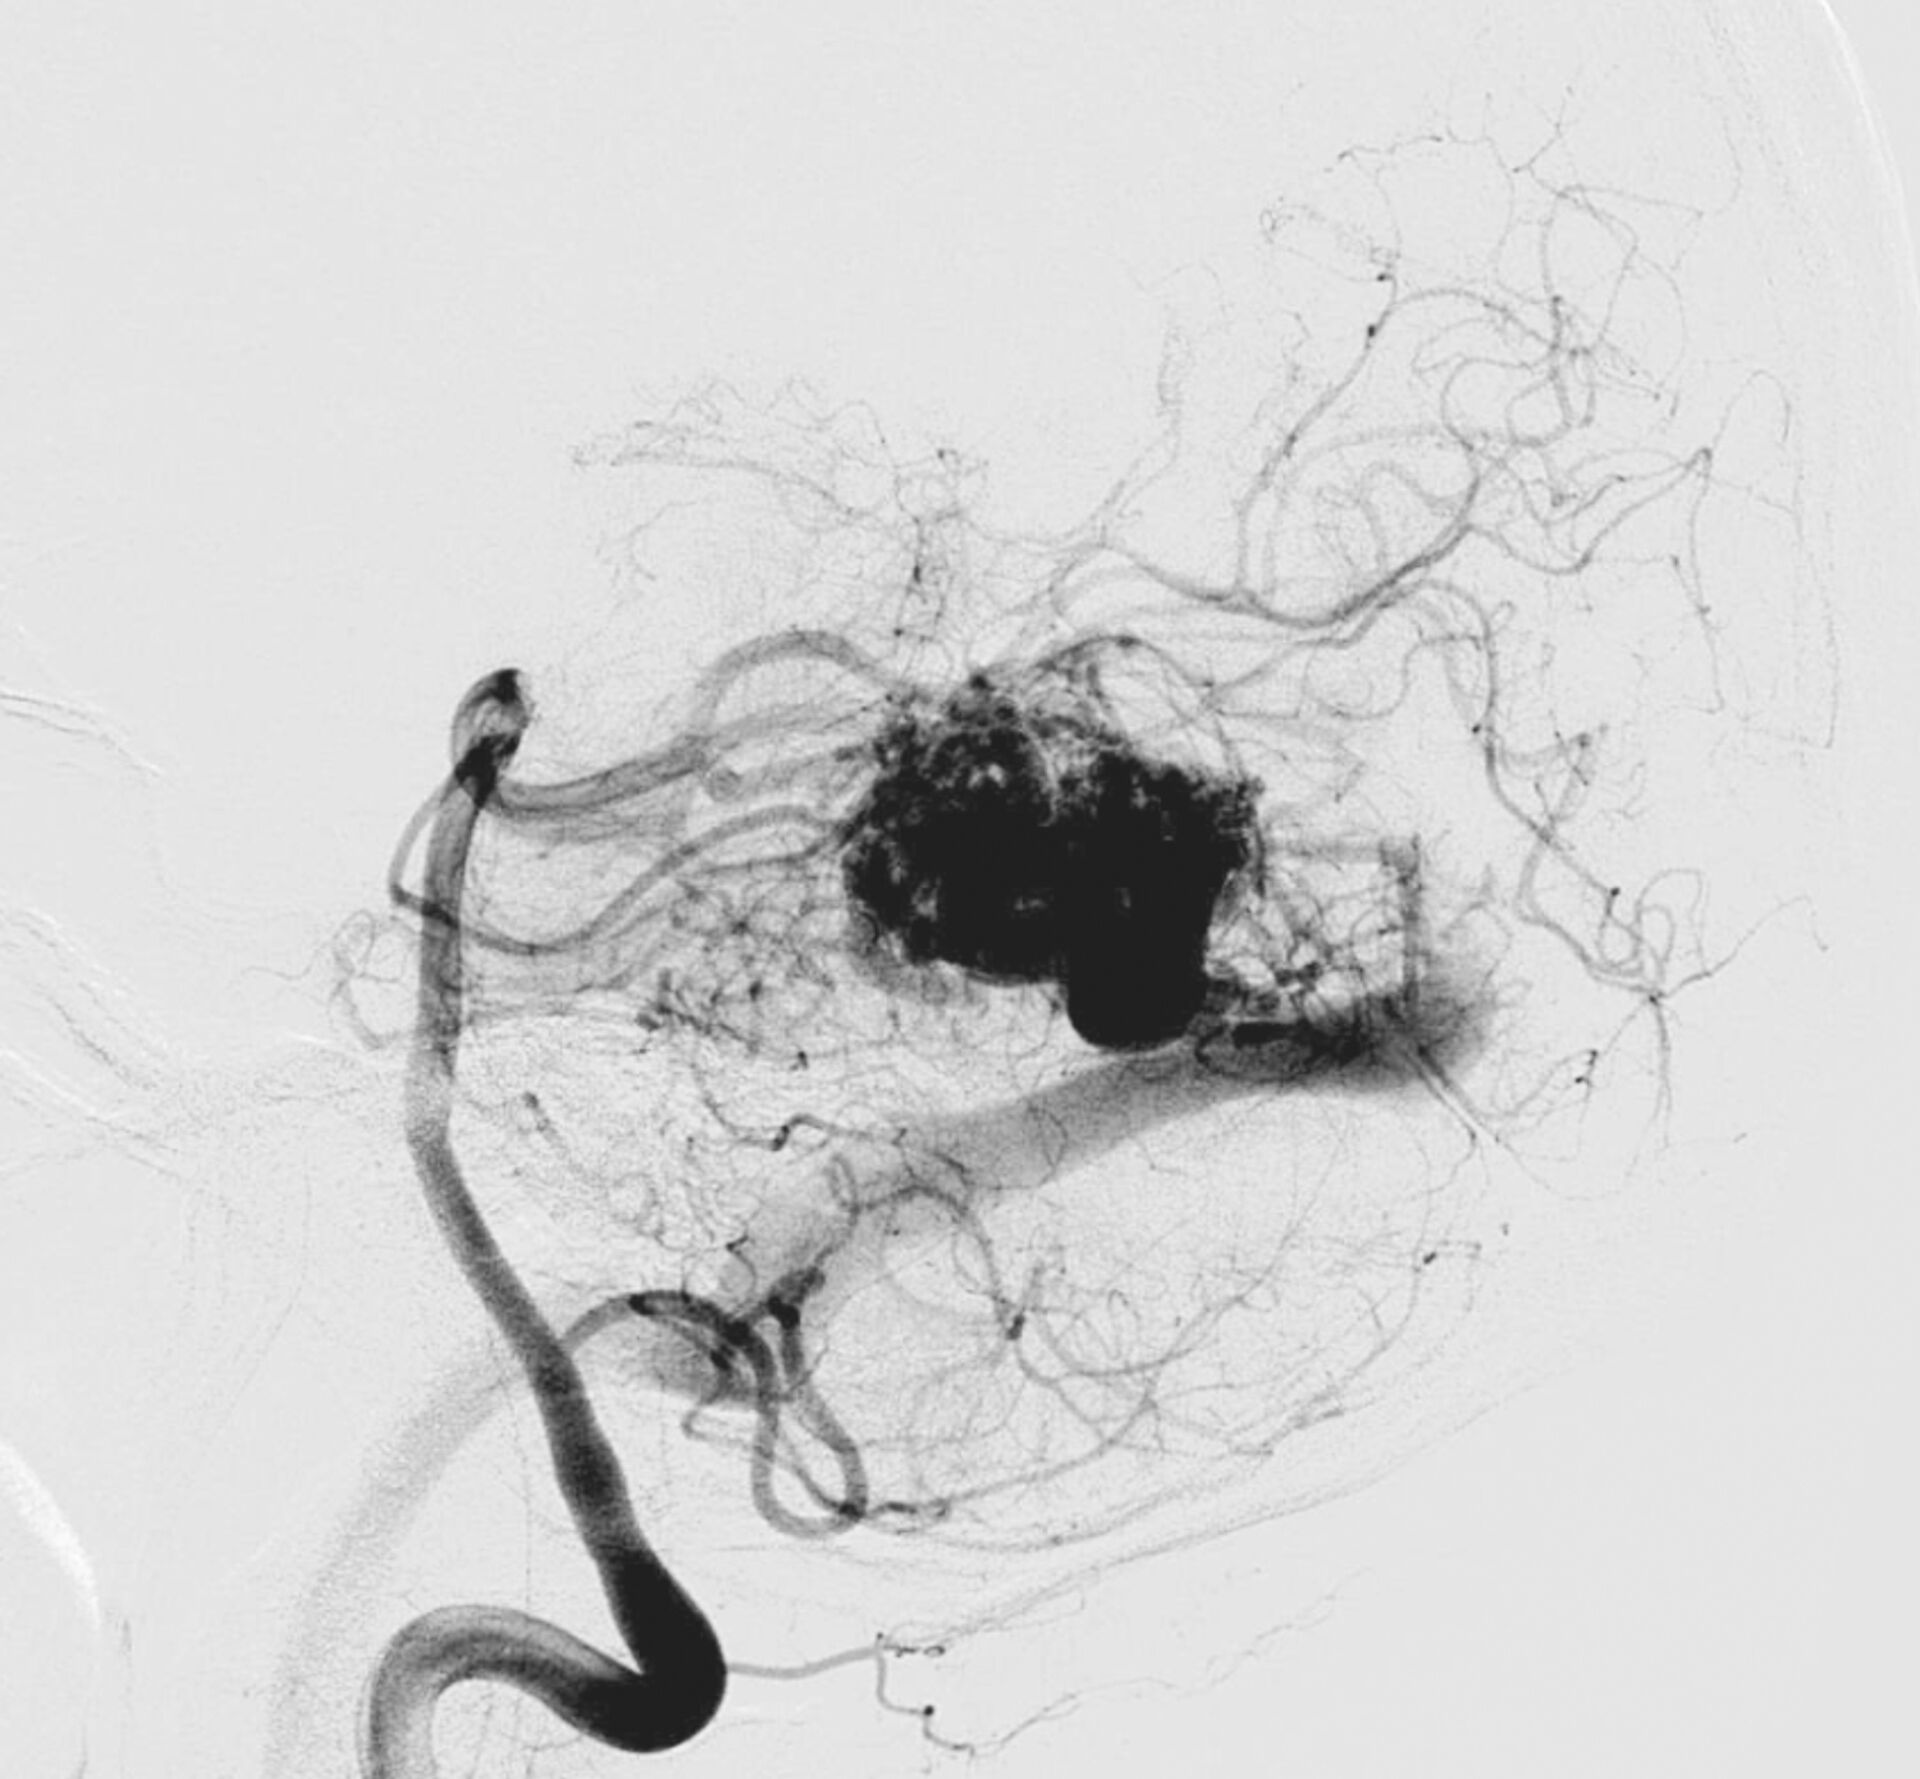

La malformation artérioveineuse (MAV) cérébrale est une anomalie congénitale rare du système vasculaire dans laquelle des artères sont directement connectées à des veines sans passer par le réseau capillaire normal. Ce court-circuit crée une circulation sanguine à haute pression dans les veines, pouvant entraîner une fragilisation progressive des parois vasculaires. Bien que certaines MAV restent silencieuses pendant des années, leur principal risque est la rupture, responsable d’hémorragies intracrâniennes parfois graves.

Le diagnostic repose sur une imagerie cérébrale complète. L’IRM permet de visualiser la malformation et ses éventuelles conséquences sur le tissu cérébral. Le scanner ou l’artériographie cérébrale précisent l’architecture de la MAV, la taille du nidus (zone de connexion anormale) et les artères nourricières. Ces éléments sont essentiels pour planifier le traitement. L’ensemble des dossiers est discuté en réunion de concertation pluridisciplinaire associant neurochirurgiens, neuroradiologues et radiothérapeutes afin d’évaluer les bénéfices et les risques de chaque option thérapeutique.